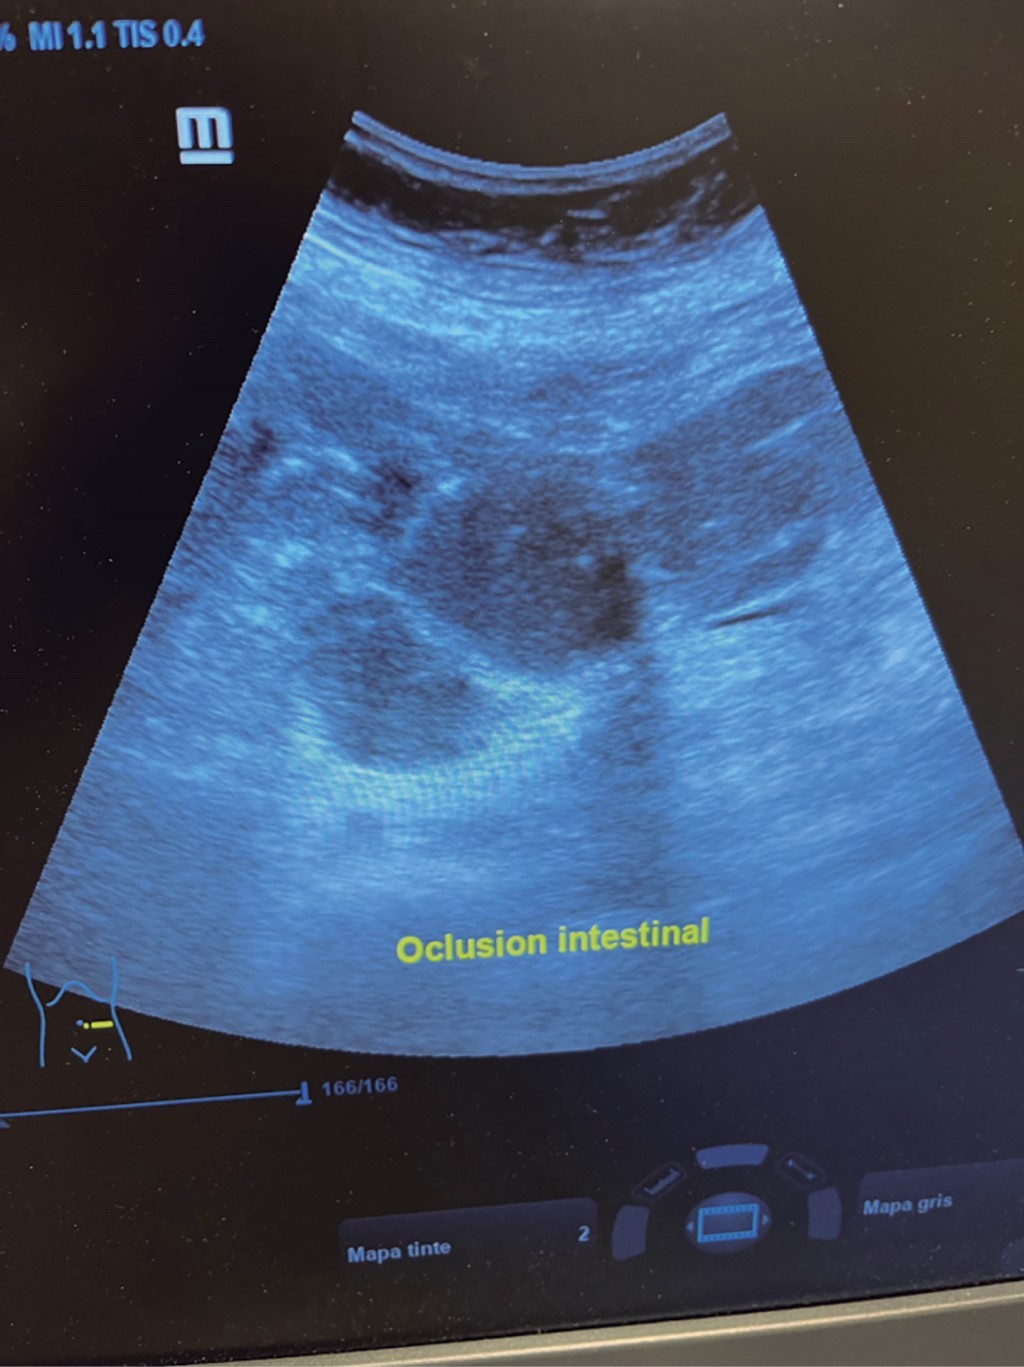

The general surgeon deals with clinical problems involving the digestive tract, the neck, the abdominal wall, and disorders of the circulatory system and the thorax. A paper published in 2008 by Lindelius,15 demonstrated that the implementation of ultrasound by the general surgeon in cases of acute abdominal pain increased diagnostic accuracy by 7.9%. In the daily consultation of the specialty, incorporating sonographic scanning to the explored area adds minutes to the clinical examination that provides data of notable value due to its objectivity and precision. The abdomen is usually the site most frequently explored by general surgeons. It is possible in a daily consultation to do the entire upper abdominal ultrasound protocol in minutes, which includes both upper quadrants and the flanks, being able to observe the liver, gallbladder and bile ducts, both kidneys, the spleen, part of the pancreas and, with the help of color Doppler, the main vessels of the region such as the inferior vena cava, abdominal aorta, portal vein, splenic vessels, and the hepatic artery. There may be limiting factors such as gastric contents, the filling level of the gallbladder, or the patient's constitution and ability to cooperate with the study. However, with daily practice, sufficient skills and refinement are acquired to achieve, with accumulated experience, images of immediate diagnostic relevance. In the training phase, contrasting our findings with information available on the web, with imaging colleagues, or surgeons already experienced in ultrasound, will allow the essential feedback and mentoring of any learning curve. Traditionally, it was considered that those organs containing a mixture of liquid and gas (intestine, stomach) are not assessable by ultrasound; the gas produces a rarefaction effect, as it does not compress the waves as a solid tissue or a liquid medium, the signals are then scattered preventing them from returning as echoes and allowing the processor to form an image congruent with the scanned organ. However, when this condition changes due to a pathological state, it is possible to identify the intestinal or gastric contents and give us a more approximate idea of what is happening in that abdomen. We can, for example, tell whether a stomach is full of liquid or whether the intestine contains solid, liquid, or gaseous residue. Today's equipment can even see the intestinal wall in detail when it is dilated. It can be distinguished when the colon is fluid-occupied at the level of the left flank as might be in amebic colitis or intestinal occlusion,16 where dilatation of the small bowel ≥ 25 mm, abnormal peristalsis, the presence of free intraperitoneal fluid and edema of the bowel wall are seen (Figure 2). In cases of acute abdominal pain, ultrasound can immediately allow differential diagnoses, such as the finding of a pyelocaliceal dilatation due to nephrolithiasis (Figure 3) or an abdominal aortic aneurysm (Figure 4). A prospective study performed in Irvine, California,17 found that the diagnostic ability of the first contact physician performing ultrasound to detect cholelithiasis has a specificity of 87% and a sensitivity of 82%, while the ultrasonography test performed by an imaging physician had a sensitivity of 83% and a specificity of 86%. In other words, by saving the patient's time, the diagnosis of cholelithiasis is feasible by adding a few minutes to the initial physical examination. In cases of appendicitis, the diagnostic method considered the gold standard is computed tomography (CT). However, it has drawbacks, such as its availability, its cost, and the risk of radiation in children and pregnant patients. In such situations, especially in children, females, or thin patients, ultrasound is a powerful tool that complements the initial clinical examination. The advantages of ultrasound over CT are its ubiquity (it is already in the emergency room), low cost, absence of radiation, and differential diagnosis with gynecologic or genitourinary causes of pain. In appendicitis, the sensitivity and specificity of CT are 99.4% and 80.0%, respectively. For ultrasound, the diagnostic sensitivity is 83% and specificity is 90%. The rate of negative appendectomy is slightly higher in the CT group than in the ultrasound group, i.e., 7.1% (3/42) (CT) compared to 4.67% (5/107) (ultrasound). It should be emphasized that ultrasound is an operator-dependent technique. Experience and quality of the equipment play an important role.18 Appendicitis has several characteristic findings, such as an edematous wall and general thickening. A noncompressible non-peristaltic tubular structure measuring more than 6 mm in diameter in the right lower quadrant is taken for criteria of positivity (Figure 5).19-21

Figure 2